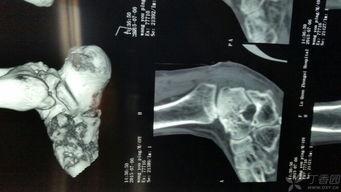

在手术之前,医生会先给你做一系列的检查,确保你的身体状况适合进行手术。这个过程可能包括X光、CT扫描或者MRI,以便医生能够清楚地看到你的脚踝骨骼情况。视频中的医生在手术前详细地介绍了这些检查的重要性,以及它们如何帮助确定手术方案。